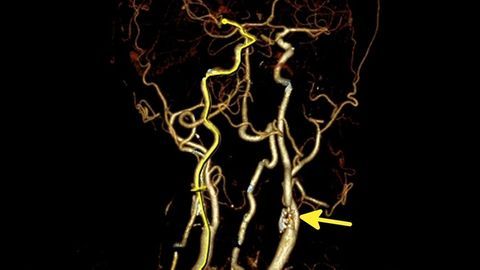

After adjusting for traditional vascular risk factors, radiologists encourage aggressive monitoring of COVID-19 patients for blood flow changes to the brain.

Emergency radiologists must be familiar with how this condition presents on CT scans.